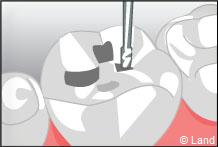

Les traitements possibles pour les stades de la carie où seuls l’émail et la dentine sont touchés peuvent se faire avec de l’amalgame qui est un matériau indiqué dans la restauration des petites et moyennes cavités.

L’amalgame est utilisé sous forme de capsules prédosées et avant son utilisation est préparé par un vibreur qui mélange les composants de façon homogène. Il se présente sous la forme d’une pâte, plastique qui durcit dans la cavité nettoyée de la lésion carieuse et devient pratiquement aussi résistant que les tissus dentaires.